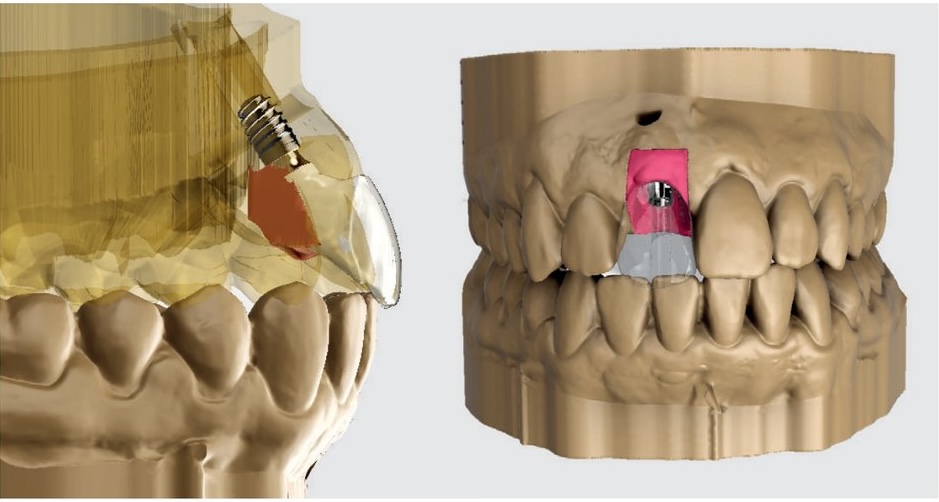

Après trois mois de cicatrisation, une empreinte optique complète de l'arcade (STL2) est réalisée sans retirer la restauration provisoire. STL1 et STL2 sont importés dans le logiciel de CAO et superposés par l'algorithme E-Merge pour obtenir un fichier fusionné (STL3) contenant la position 3D de l'implant, le contour péri-implantaire et le profil d'émergence complet. Ce fichier sert à concevoir la restauration définitive et à imprimer le modèle de travail.

Situation clinique 1 — fusion STL, modèle imprimé et conception de la couronne définitive